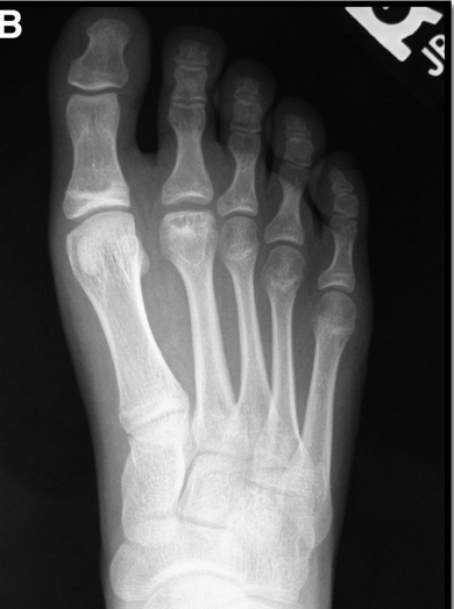

Freiberg病,又称跖骨头无菌性坏死或跖骨头骨软骨病,由Freiberg于1914年首次报道;关于Freiberg病的国内报道较少,与许多骨科医师对此病的认识不够深入进而引起误诊、漏诊有关。共同的病理变化包括跖骨头扁平、塌陷,继而发生跖趾关节的退行性变,并最终演变为跖趾关节骨关节病。

Smillie分期共有5期:

• Ⅰ期:干骺端的血供已遭破坏,出现裂缝骨折,周围松质骨开始硬化,但没有明显的外在表现;

• Ⅱ期:跖骨头中心硬化的松质骨被吸收,背侧软骨开始向跖侧塌陷,跖趾关节面的轮廓发生改变;

• Ⅲ期:随着骨质被进一步吸收,软骨继续向跖侧塌陷,但跖侧的软骨仍相对完整;

• Ⅳ期:整个跖骨头塌陷,部分关节软骨开始脱落,关节面的解剖结构已无法重建;

• Ⅴ期:跖趾关节炎明显,跖骨头已变扁平,仅跖侧的关节软骨可能仍部分保留原始的外形轮廓

影像学表现

早期

晚期

1、跖骨头区域疼痛,行走后加重2、跖骨头区域直至整个趾头肿胀3、趾头可能会翘起,甚至畸形4、跖趾关节活动度差5、跖骨头下胼胝体形成6、早期,跖骨头或跖趾关节处压痛可能是唯一症状

诊断方法:病史+X线片检查结果,是否需要进一步做CT或MRI检查以进一步明确病变程度,从而决定手术方式